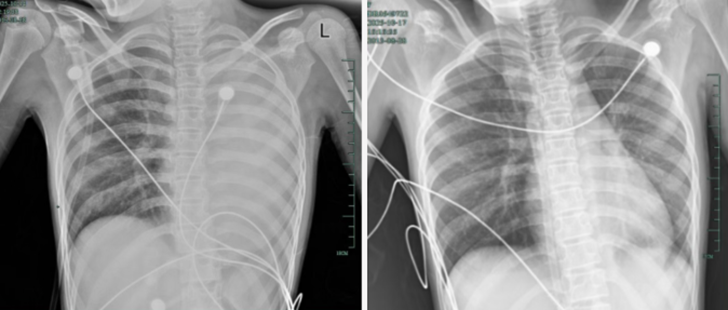

治疗前后影响对比,左肺从“白肺”到正常状态

呼吸急促、胸闷胸痛,体温38.5℃,只能靠5L/min的面罩吸氧维持血氧,胸片显示左肺已完全呈 “白肺” 改变,肺部炎症进展迅猛。